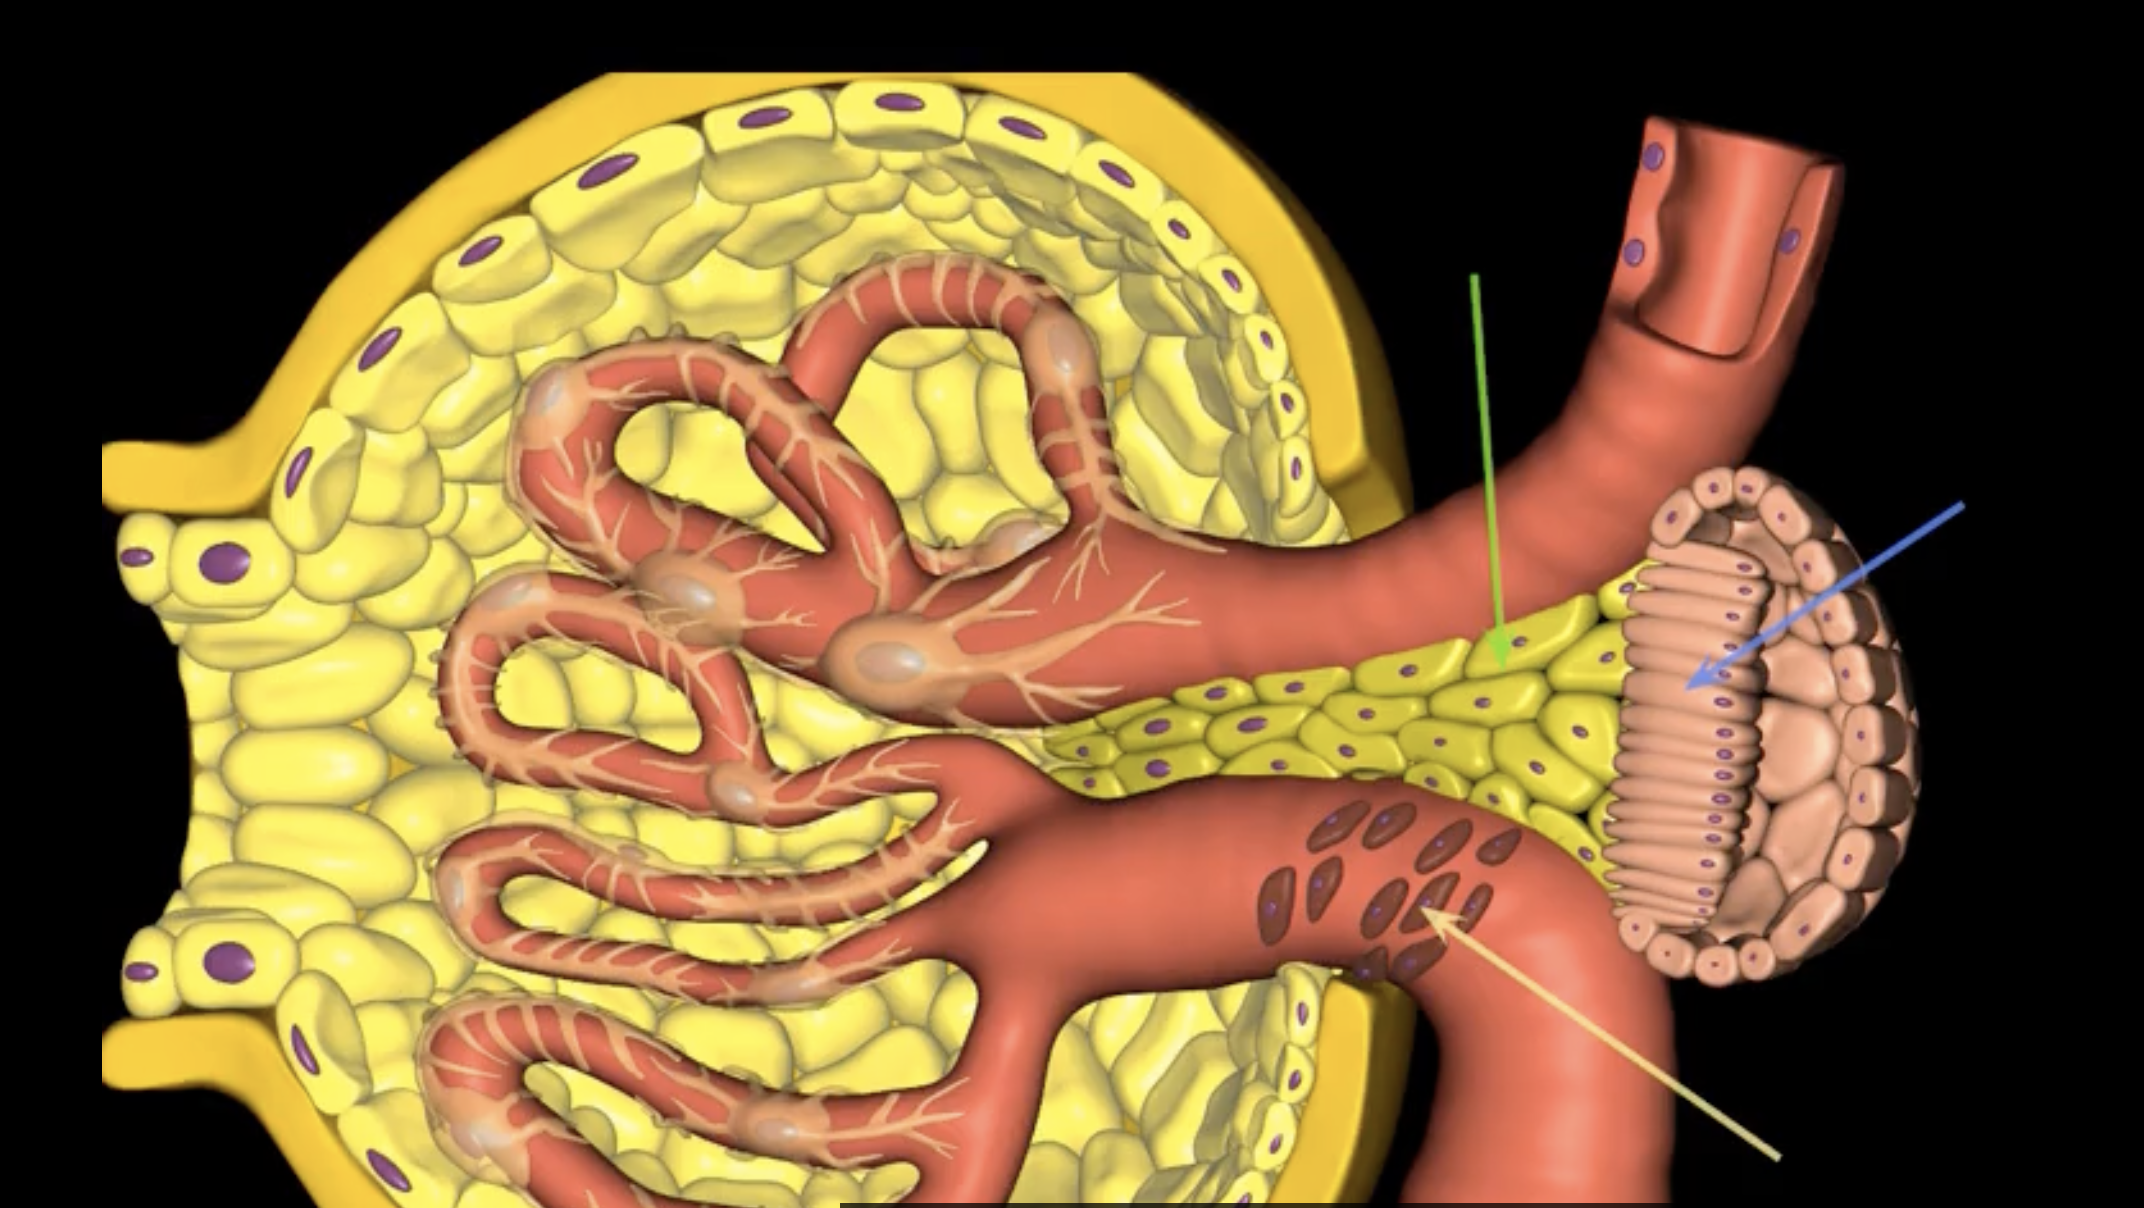

juxtaglomerular structure

juxtaglomerular (granular) cells, modified smooth muscle cells, release renin in response to signals from macula densa

yellow arrow

macula densa

blue arrow

extraglomerular mesangial cells

green arrow

macula densa, modified columnar epithelium

juxtaglomerular cells

If macula densa detect a decrease in ion concentration, then they stimulate _____ cells to release renin which actives RAAS